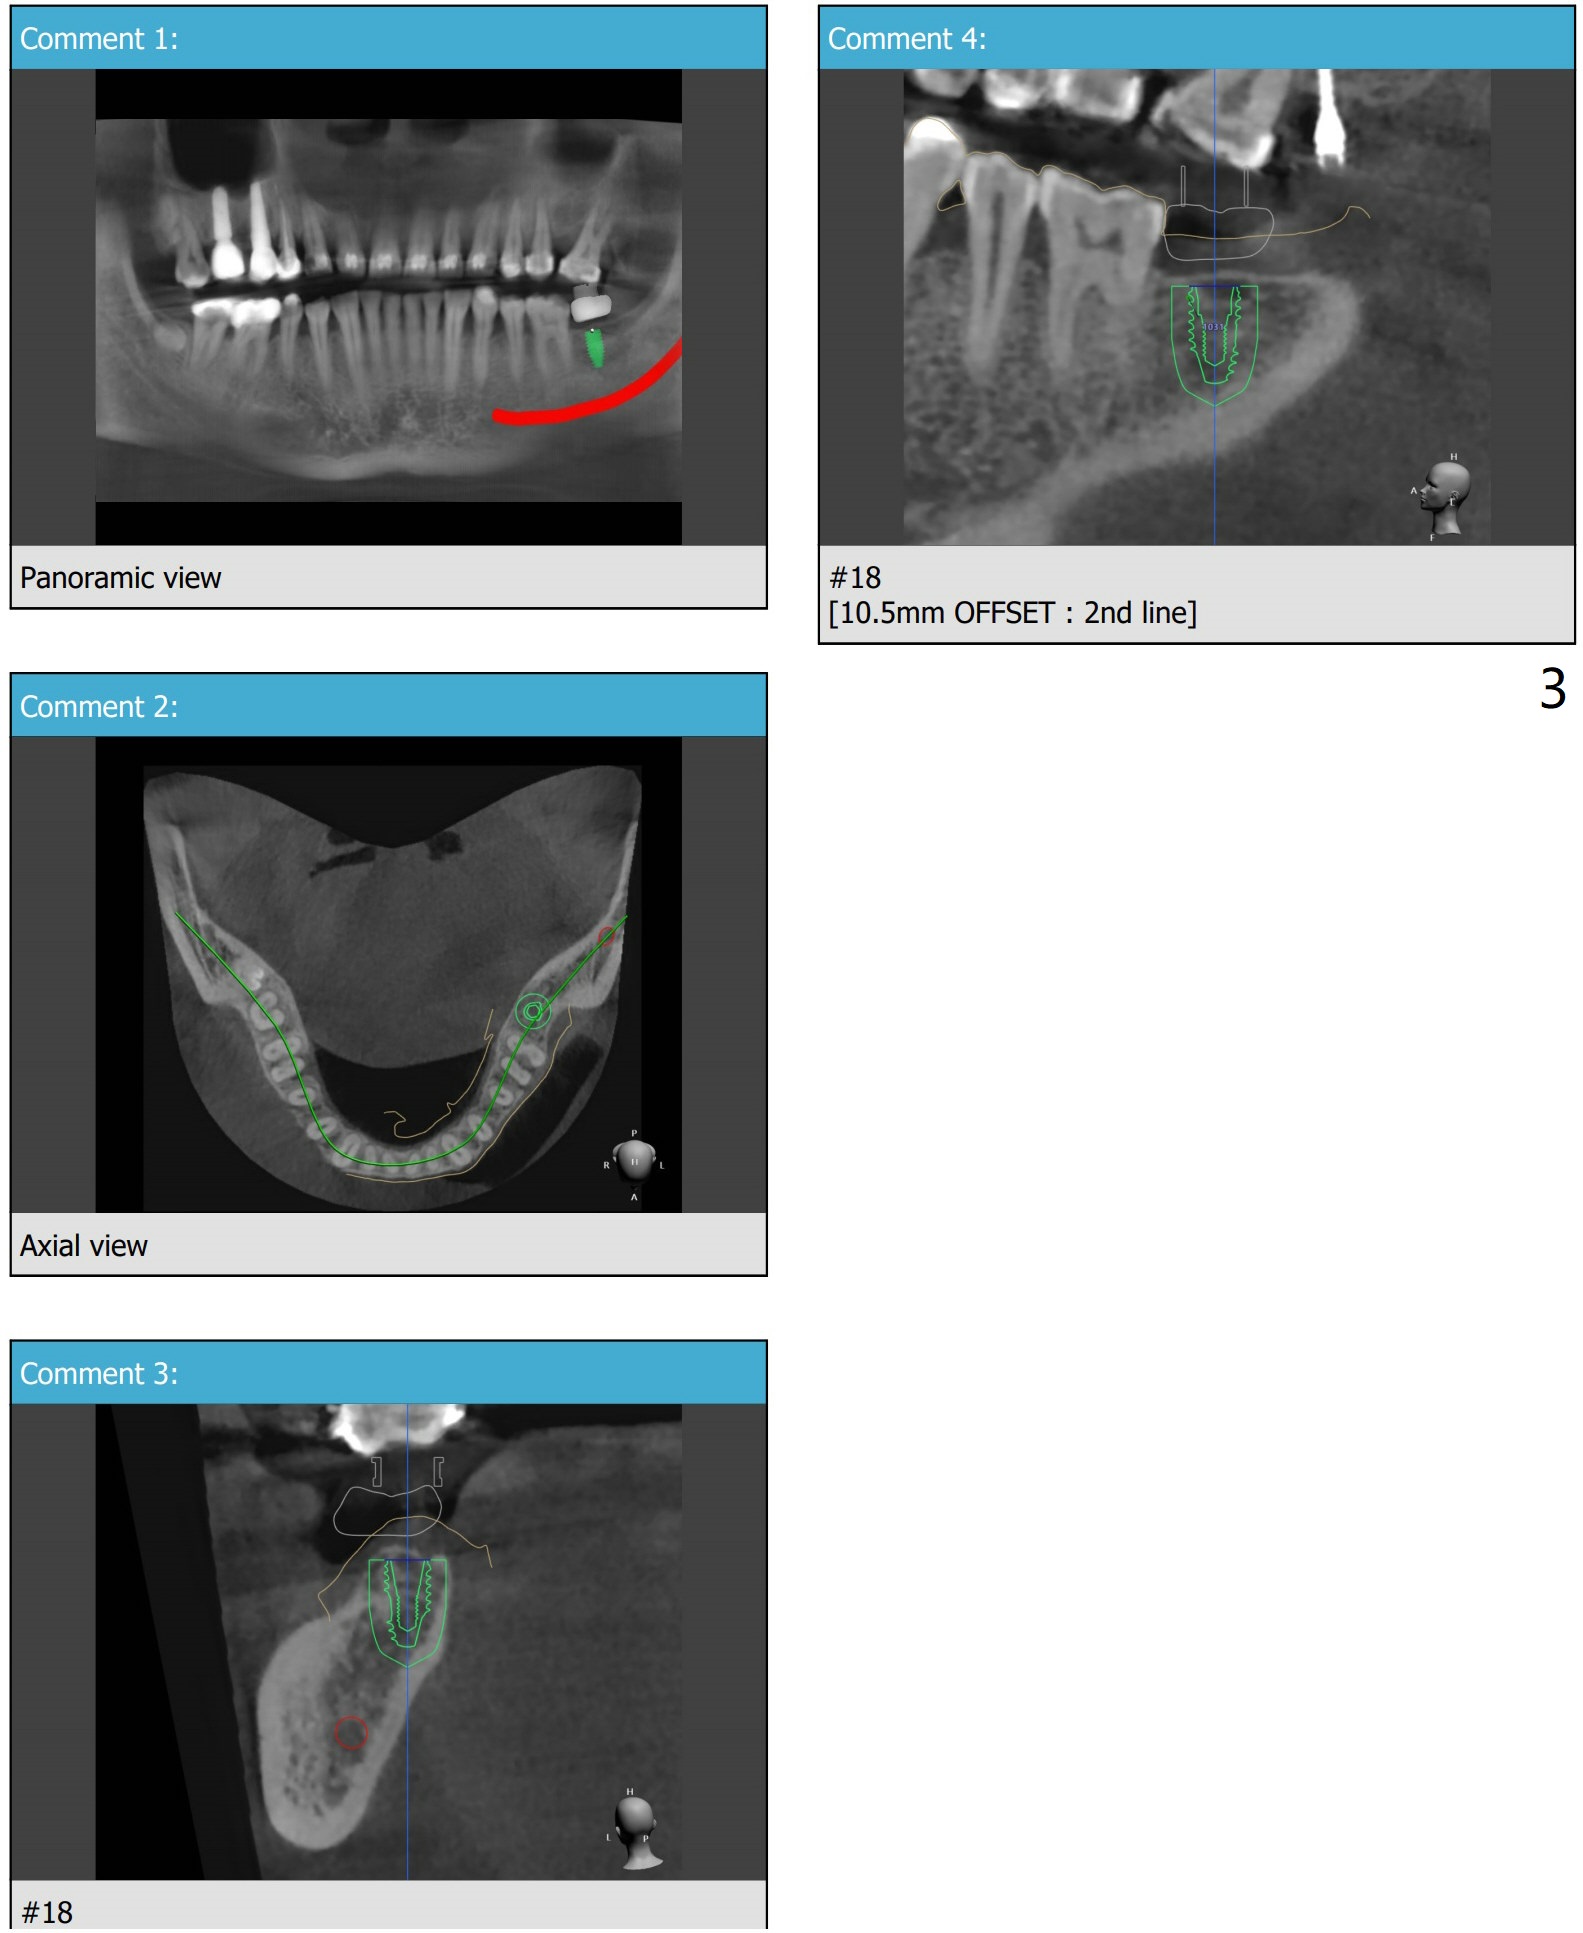

厚舌侧骨板

54岁男为了利用保险,在没完成上颌牙齿矫正前,做左下7种植。由于厚的舌侧骨板阻挡,植体稍微小些短些(5x10与4.5x8.5毫米)。